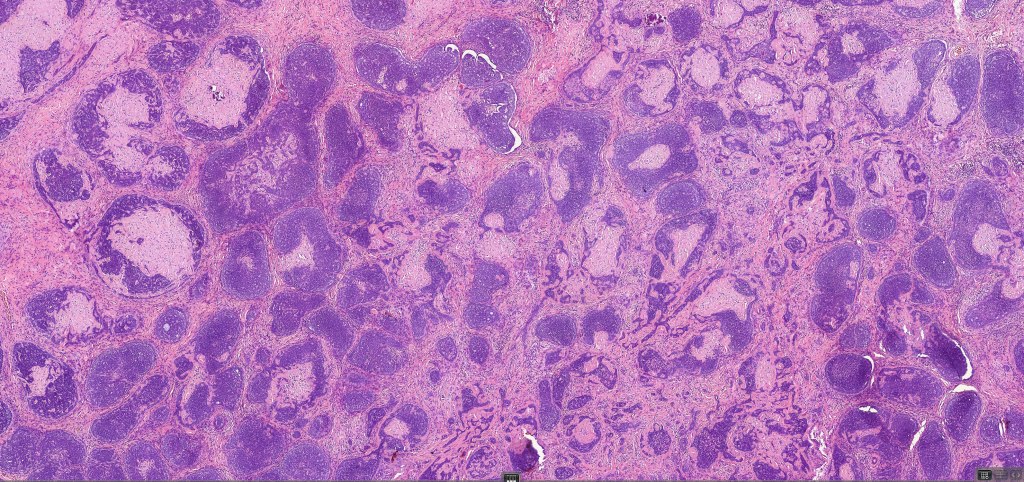

•Sharply circumscribed, unencapsulated nodule in deep dermis +/- subcutaneous fat or deeper (trichoepithelioma is much more superficial)

•Variably sized but generally large, basophilic tumor nodules composed of small uniform basaloid cells with minimal cytoplasm

•A rich fibromyxoid mesenchymal stroma with variable papillary mesenchymal bodies (sometimes these are absent)

•Variants include cystic, rippled pattern, pigmented, clear cell, trichoblastoma with ductal differentiation & trichoblastoma with sebaceous differentiation